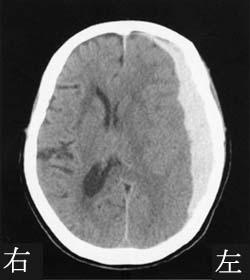

右内包後脚では、左上下肢の運動麻痺が見られるため、この選択肢は正しいです。